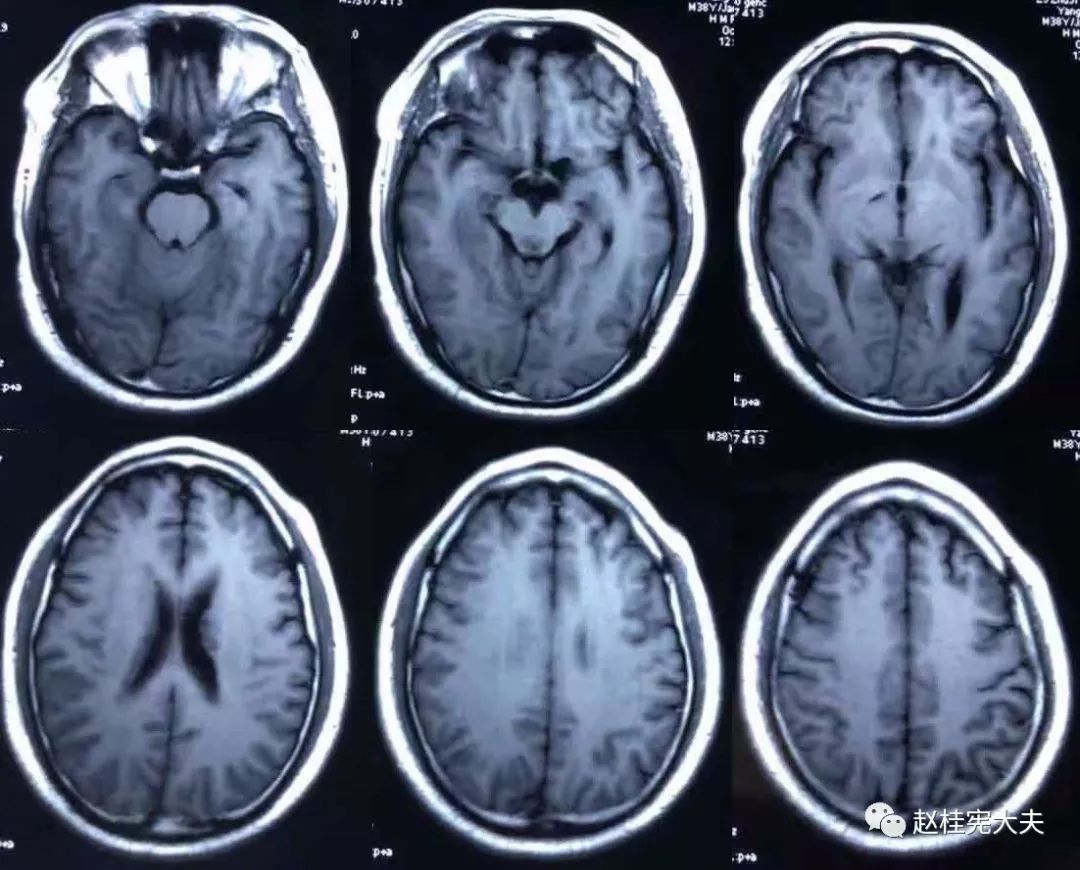

2018.7.6头颅MRI:胼胝体、穹隆及双侧脑室旁、基底节区、右侧延髓、桥臂异常信号,脱髓鞘病变考虑。头颅MRS:左枕叶病变区MRS显示:NAA下降,Cho升高,Cho/NAA=3.86,并见倒置乳酸峰。

7.20复查头颅MRI平扫:胼胝体、穹隆及双侧脑室旁、基底节区、右侧延髓、桥臂广泛信号异常,对照前片(7.10)范围明显缩小。

2018.10复查头颅MRI:胼胝体压部、左侧部分枕颞叶、侧脑室枕角旁、中脑脱髓鞘病变,视神经脊髓炎谱系病?结合对照前片(7.4)病变范围有所缩小。

我看到患者时的思考:当了解了患者前期诊疗经过后,在看到患者磁共振片子时,我的第一反应就是淋巴瘤。尽管患者激素治疗后症状有好转,病灶在磁共振上看起来也是有好转,但淋巴瘤也会出现这样的表现。

我对满脑室边的病灶的体会是:遇到这样的病例,首先要考虑感染、肿瘤(如室管膜瘤、生殖细胞瘤、淋巴瘤或转移瘤脑室播散等等),炎症要放到后面去考虑,脱髓鞘的诊断要打个大大大大的?。炎症中,血管炎不像,自免脑也不是很支持,尽管边缘系统似乎也有受累,但患者边缘叶脑炎的精神、行为异常、癫痫等症状很少,而且磁共振上看去除了边缘系统,整个脑室系统都有受累,这个和常见自免脑不符。视神经脊髓炎谱系病?尽管病灶在水通道蛋白富集区,但这样的视神经脊髓炎(视神经和脊髓均未受累,近脑室边的异常信号)至少罕见,即使诊断,也应该是排除其它的疾病后才可能考虑。